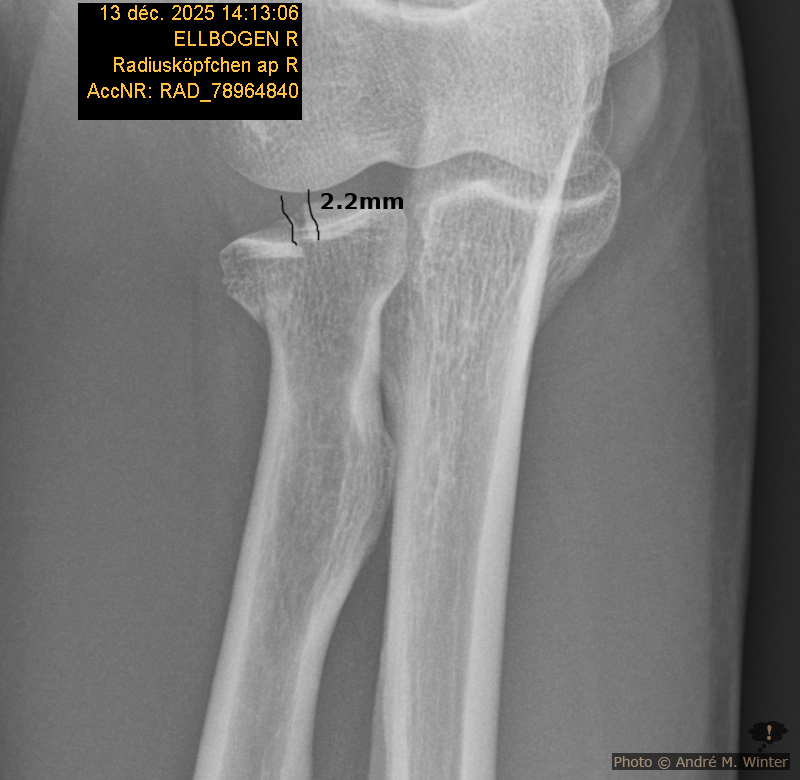

In der Nacht gehe ich vom Ehebett ins Wohnzimmer wo ich meine, den Arm besser lagern zu können. Aber an Schlafen ist nicht zu denken. Ich frühstücke, dusche noch mal und fahre Samstag den 13. Dezember 2025 mit einer Armbinde auf die Notfallambulanz. Hier fragt man mich, warum ich nicht gleich gekommen sei. Ich antworte, dass der Unfall am selben Tag passiert sei, halt kurz nach Mitternacht. Das hat jedoch nichts am später diagnostizierten Bruch geändert. In einem ersten Röntgen ist fast nichts im Ellbogen, der vorrangig schmerzt, zu erkennen. Der Aufnahmewinkel lässt anscheinend die Teile so erscheinen als wären sie gut beisammen, man sieht nur einen Schleier im Knochen. Ein zweites Röntgen bringt Klarkeit. Durch den Sturz landete das ganze Körpergewicht auf der rechten Hand. Diese hielt stand. Der Schlag setzte sich bis in den Ellbogen fort wo das sog. Radiusköpfchen brach. Der Radius ist die Speiche, also der obenliegende Knochen des Unterarms. Dieser endet im einer Hohlform die am Oberarmknochen über ein Köpfchen greift, dieses aber nicht umschliesst und bei starken Armverdrehungen sich aus “auskuppeln” kann (im Gegensatz zur besser verankerten Elle). Anscheinend war dies beim Sturz der Fall und die Halbholform traf nicht genau auf das Köpfchen gegenüber. Ein Teil der Halbholform brach aus und verschob sich über 2 Millimeter nach hinten.

Radiusköpfchen und abgebrochene Stelle

Diesen Versatz sah man dann im zweiten Röntgen, welches mit 45 Grad in den Ellbogen aufgenommen wurde. Der Spalt war grösser als 2 Millimeter, aber nur knapp. Das nennt man fachlich Radiuskopffraktur rechts Mason Typ II. An dieser Grenze wird entschieden ob man eine konservative Verheilung anstrebt oder ob operiert werden muss. Über 2 Millimeter muss normalerweise operiert werden aber es gibt nur um eine par Bruchteile Millimeter darüber. In der Notfallambulanz der Klinik Innsbruck will man die Entscheidung der Handambulanz überlassen und man verpasst mir einen Spaltgips von der Hand bis zur Schulter über den Rest des Wochenendes. Der Spalt bedeutet nicht dass er abnehmbar ist, er ist bloss ein wenig leichter. Ich war ganze 6 Stunden dort. Aber auch mühsam verletzte (Schulterbruch) liess man so lange warten.